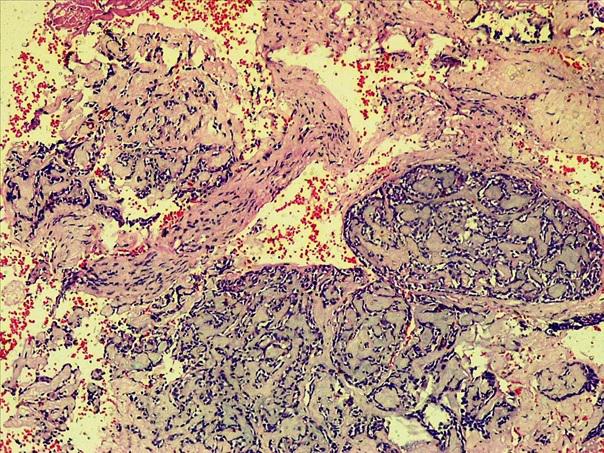

*Case 3 : Pr Modupeola Samaila/ Dr Rimamscep Ifusumu

email: mamak97@yahoo.com

Clinical detail: Female, 38 years. Orbital cystic tumour of 2 years duration.

Clinical diagnosis is orbital tumour query mucormycosis.

Please, consult the virtual slides of Case 3 below.